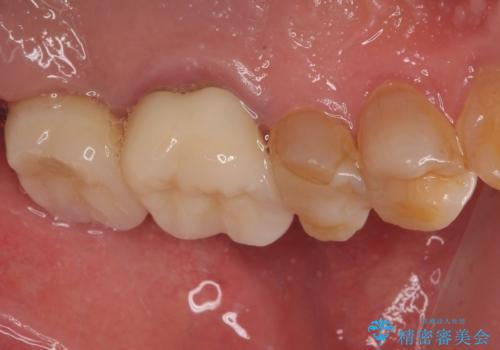

欠損した奥歯 インプラントによる補綴治療

- 破損したクラウンと、奥歯の欠損を気にして来院された患者様です。

奥歯の欠損部はインプラントによる補綴治療を、手前の破損したクラウンは作り替えをご希望でした。

しかしながら、レントゲンやCT画像から、手前の破損したクラウンの根尖部に大きな病変が認められ、インプラント埋入部にまで病変が及んでいることから、まずは手前の根管治療を行い、病変の正体を確認した後にインプラント埋入を行うこととしました。

口があまり開かず、インプラントの埋入角度がやや斜めとなりましたが、機能的には全く問題なく治療を終えることができました。